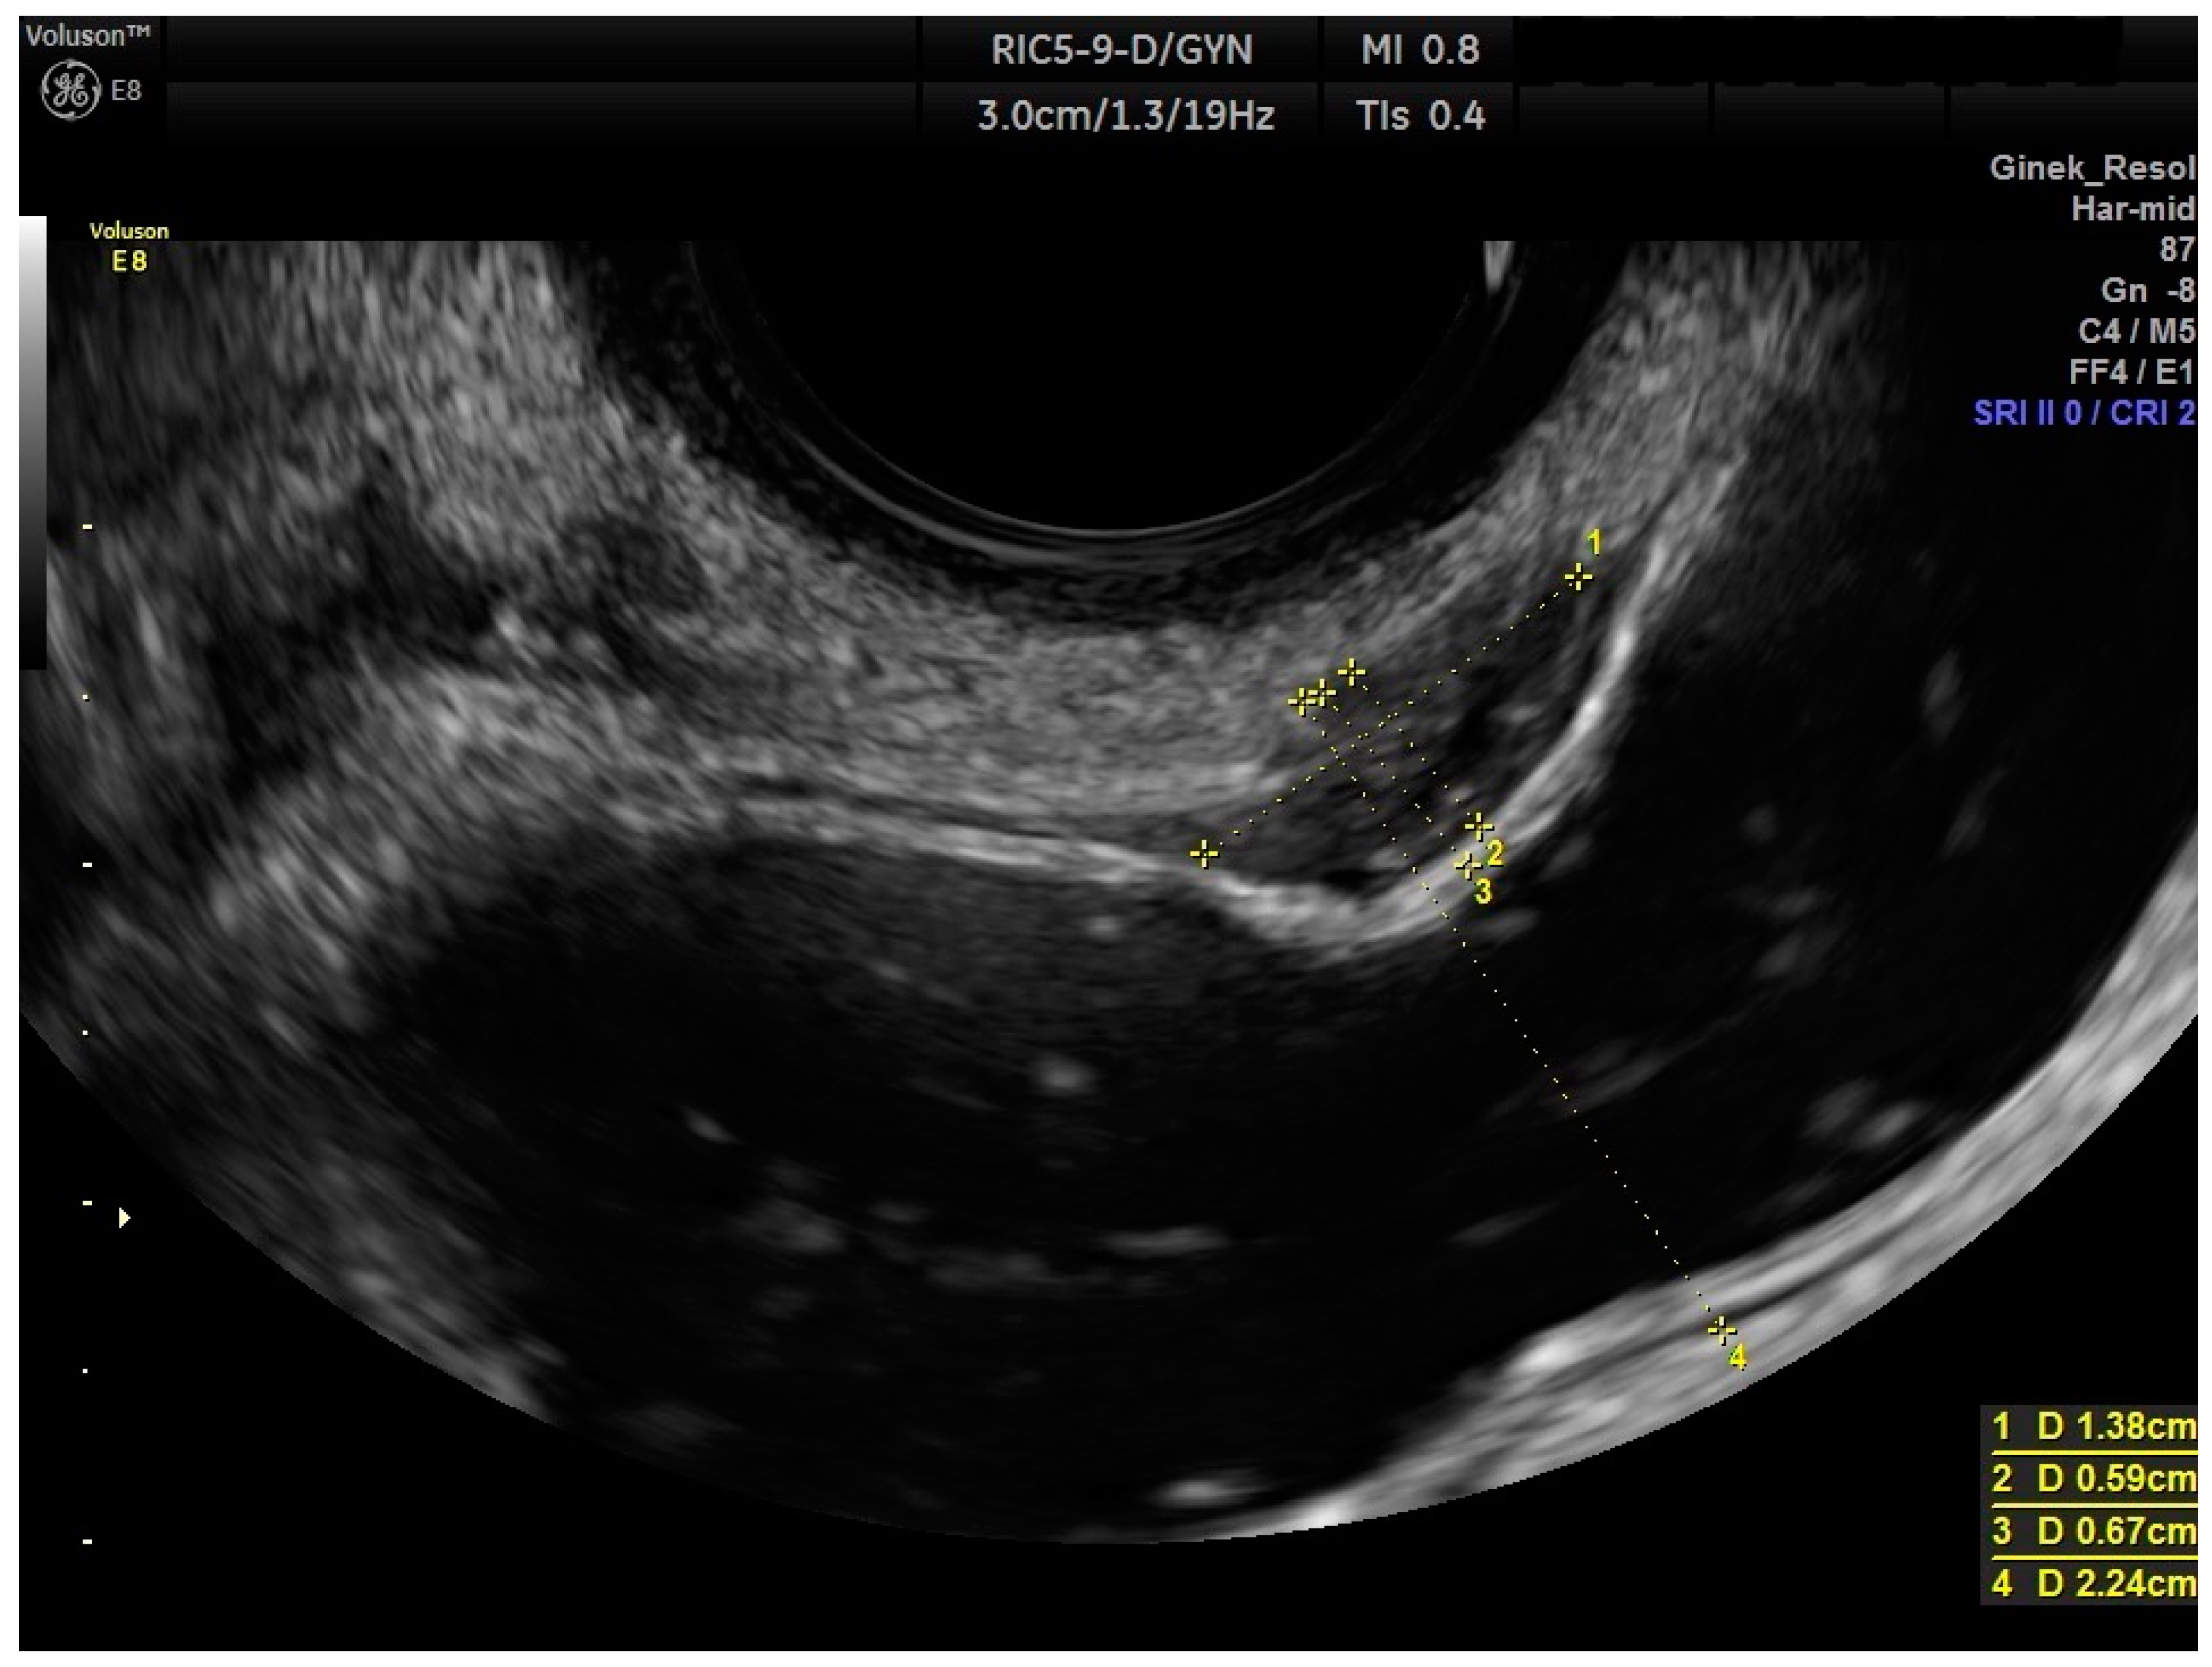

2.2. Ultrasound Measurements

| RWC-TVS greatest size (mm) | 23.613 | 0.00 | 45.00 | 9.42 | 0.94 |

| HPE greatest size (mm) | 26.033 | 8.00 | 90.00 | 18.49 |